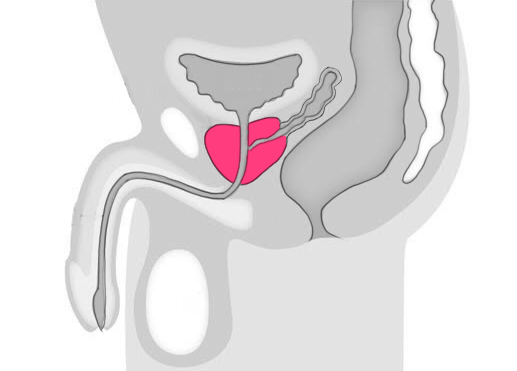

前立腺がんは、男性の生殖器官である前立腺に発生するがんを指します。

手術中には、前立腺の位置や大きさ、周囲の組織との関係を確認しながら、がん組織をできるだけ取り除きます。